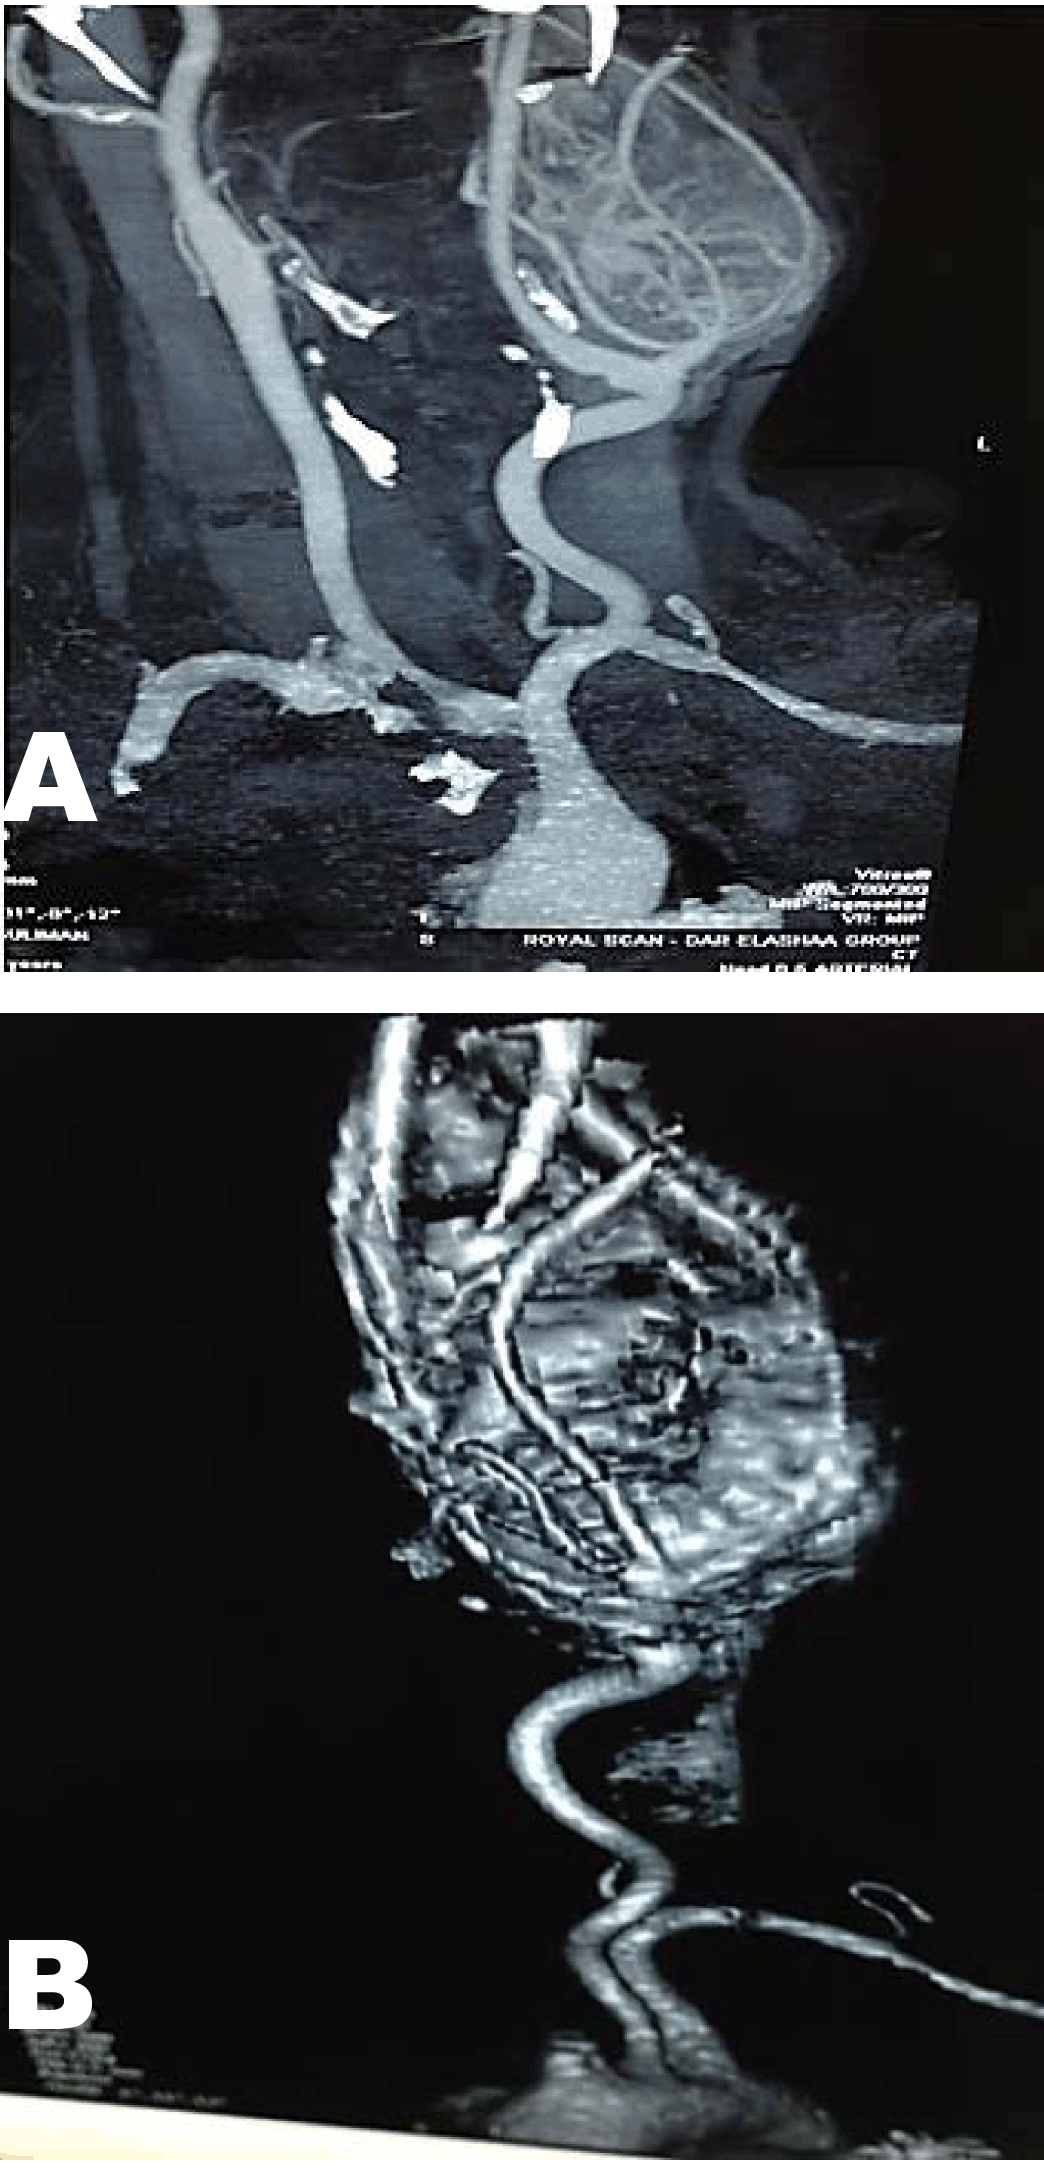

Systemic examination revealed no signs of neurological or vascular deficit computed tomography angiography (CTA) and magnetic resonance angiography (MRA) of the carotid vessels showed a mass arising at the bifurcation of common carotid artery (CCA), which has rich blood supply, splaying the external carotid artery (ECA) (Figure 1). Blood test for vanillylmandelic acid (VMA) was negative.

Figure 1: Imaging studies (A) MRA (B) Computed tomography angiography showing a carotid body tumors arising at the bifurcation of common carotid artery, which has rich blood supply, splaying the external carotid artery.